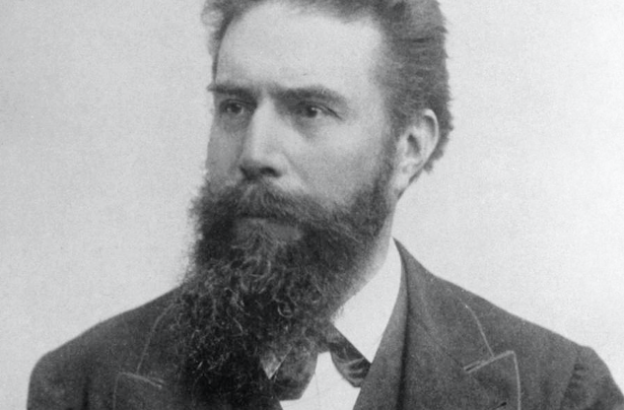

Tutto su Wilhelm Conrad Röntgen, il fisico che scoprì i raggi X

Oltre un secolo fa, un fisico tedesco stava per rivoluzionare il mondo scientifico: era Wilhelm Conrad Röntgen, primo premio Nobel per la fisica.

Biografia di Wilhelm Conrad Röntgen, il fotografo dell’invisibile

Wilhelm Conrad Röntgen nacque il 27 marzo 1845 a Lennep, nella regione del Basso Reno, in Germania. Poiché unico figlio di Friedrich Conrad Röntgen, produttore e commerciante tessile discendente di un’antica famiglia di mercanti, Wilhelm avrebbe un giorno ereditato il mestiere del padre muovendosi tra stoffe dai colori tenui o sgargianti, operate, tinte o di gusto assolutamente classico. Ma non fu così.